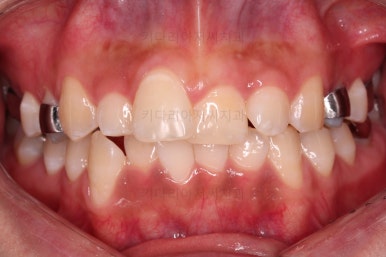

마찬가지로 초진 시 얼굴모습입니다.

아래턱이 좌측으로 굉장히 많이 틀어진 안면비대칭이 있는 상황이었어요.

턱뼈가 한 쪽으로 치우치다 보니 입술과 치열도 함께 기울었어요.